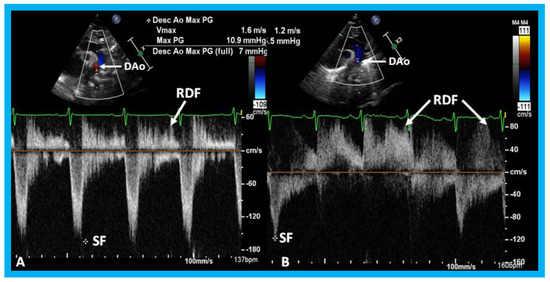

Lastly, in small PDAs, normal diastolic anterograde flow is seen descending aorta (Figure 34), while in large PDAs, either no normal anterograde diastolic flow or retrograde diastolic flow (Figure 35) is seen in the descending aorta. Most of the medium-sized PDAs have normal diastolic anterograde flow in the descending aorta.

Back to TopTop